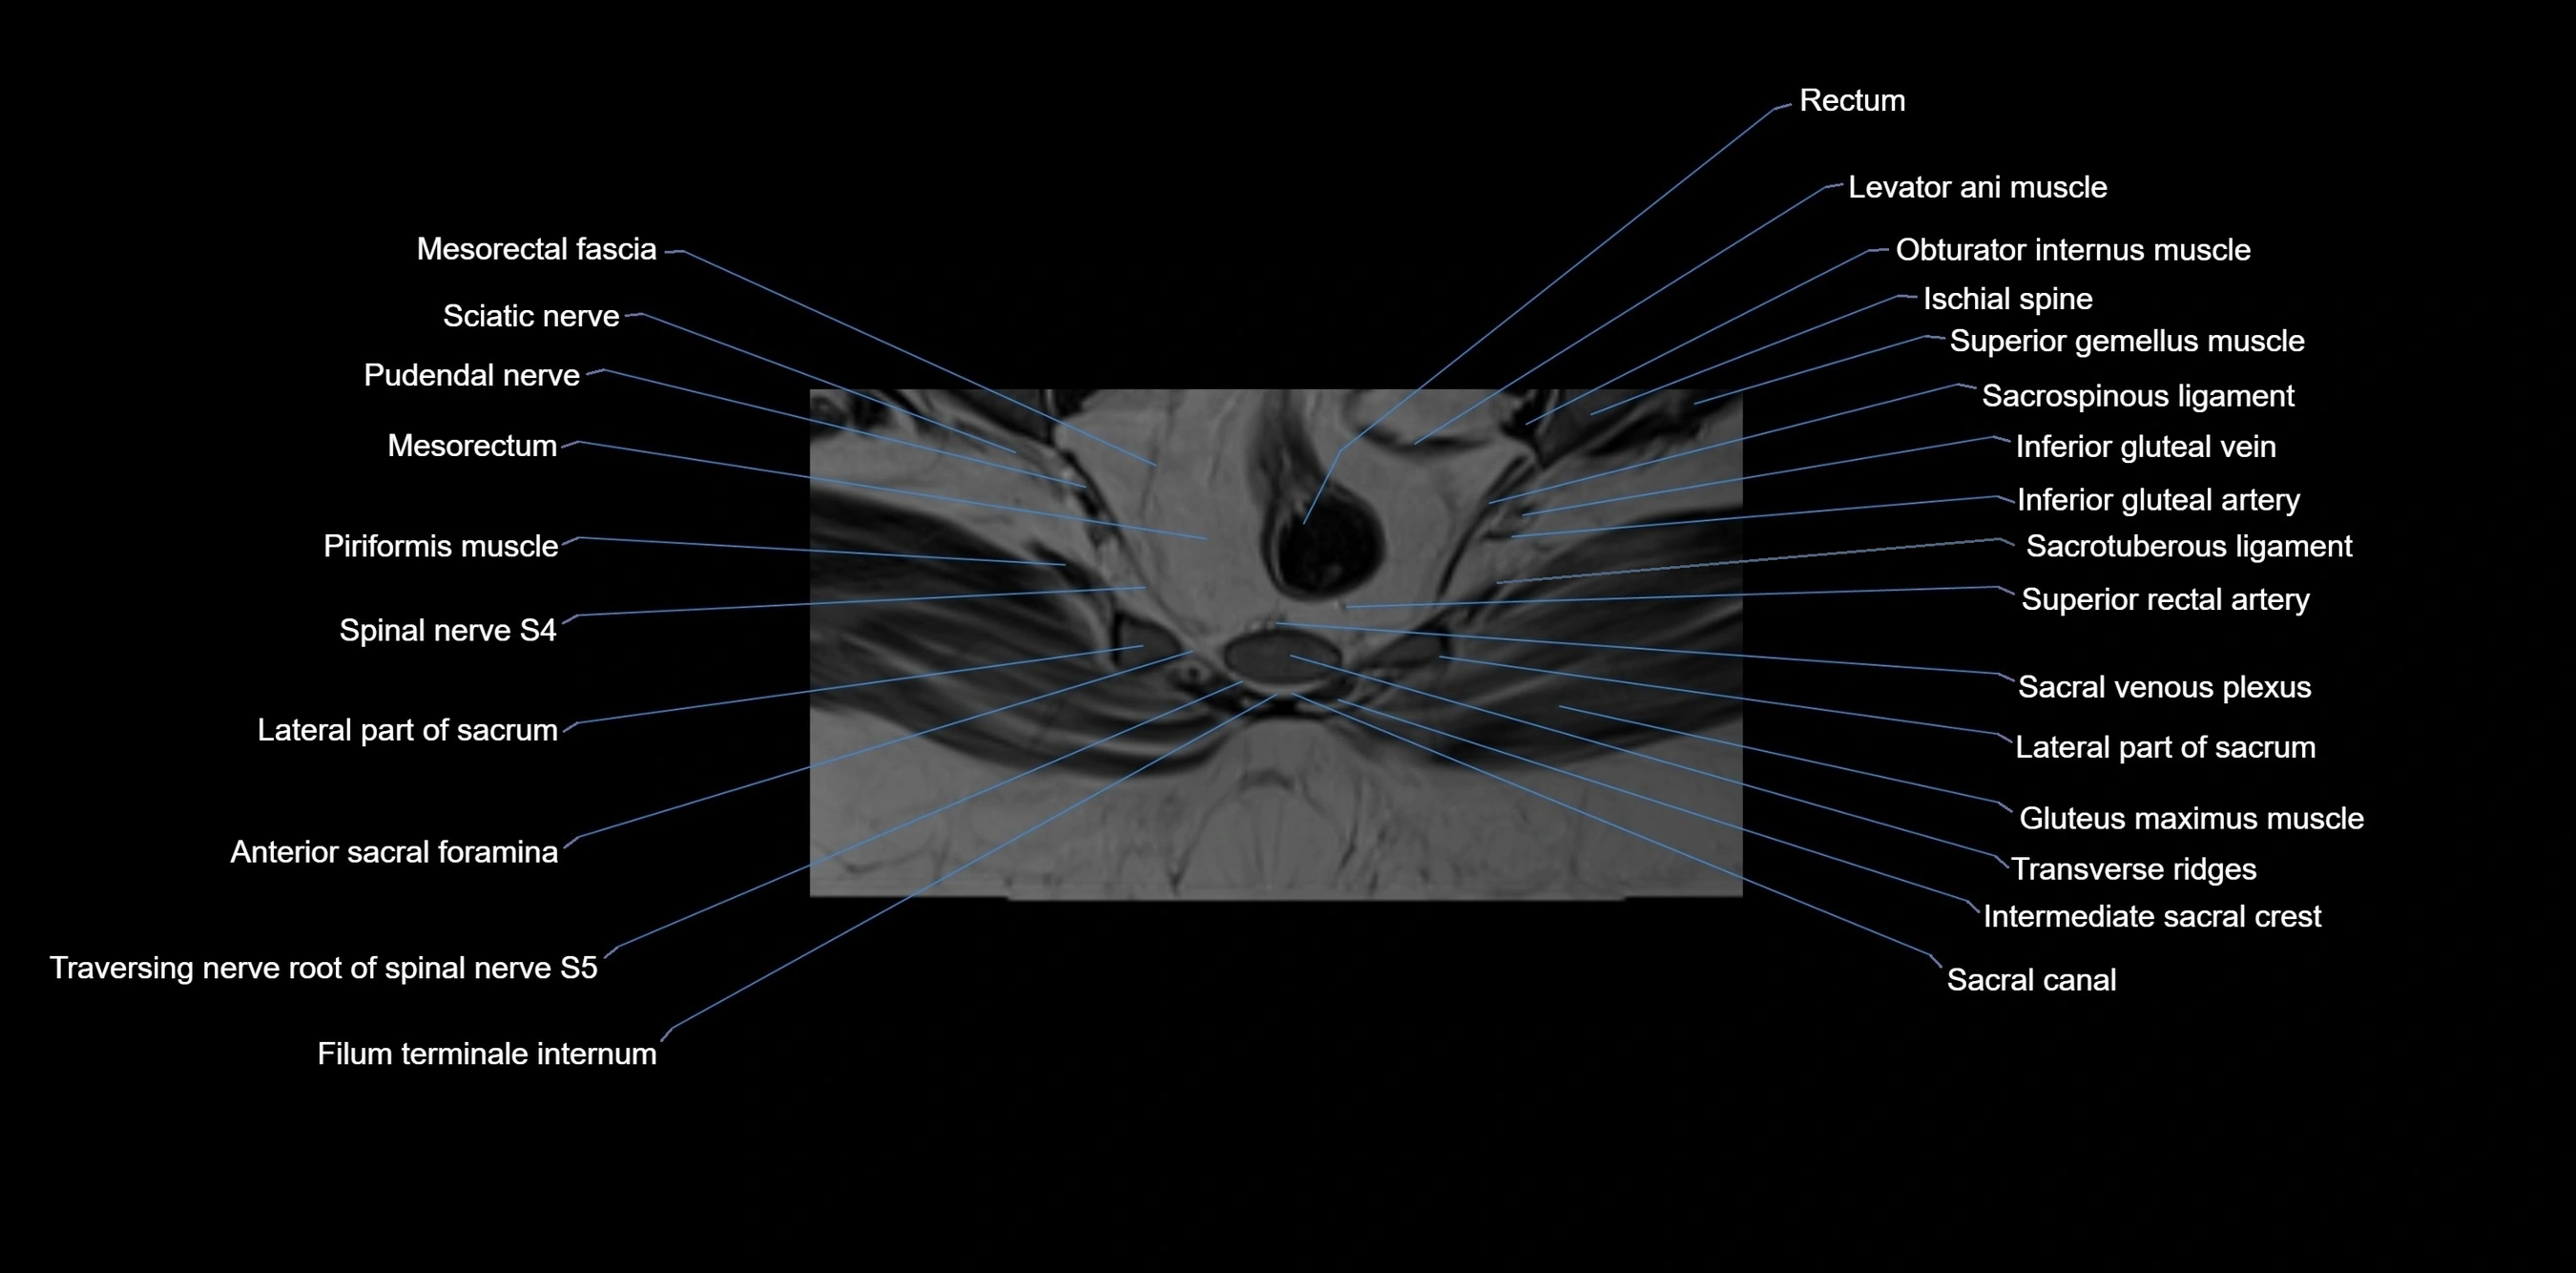

CT image

image